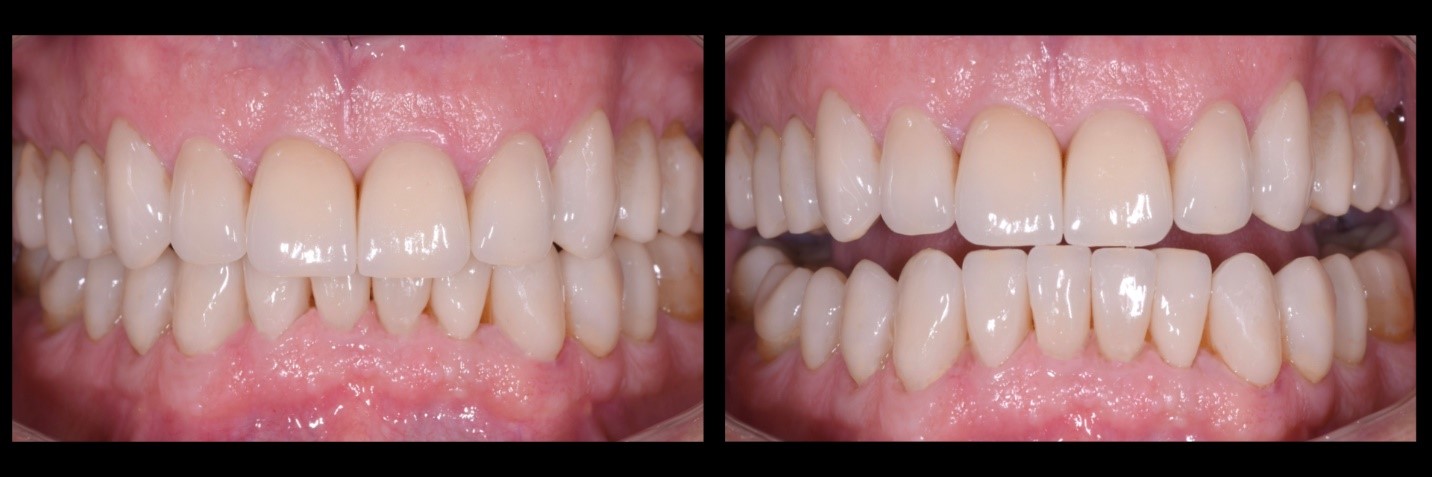

Fig. 1a e 1b

Il Paziente, di anni 69, si presenta alla mia osservazione con forti limiti estetico-funzionali dovuti a dentatura fortemente usurata.

Fig. 8a e 8b

Integrazione dei restauri in disilicato di litio monolitico all’interno del sorriso del paziente in massima esposizione, rispetto alla situazione iniziale.